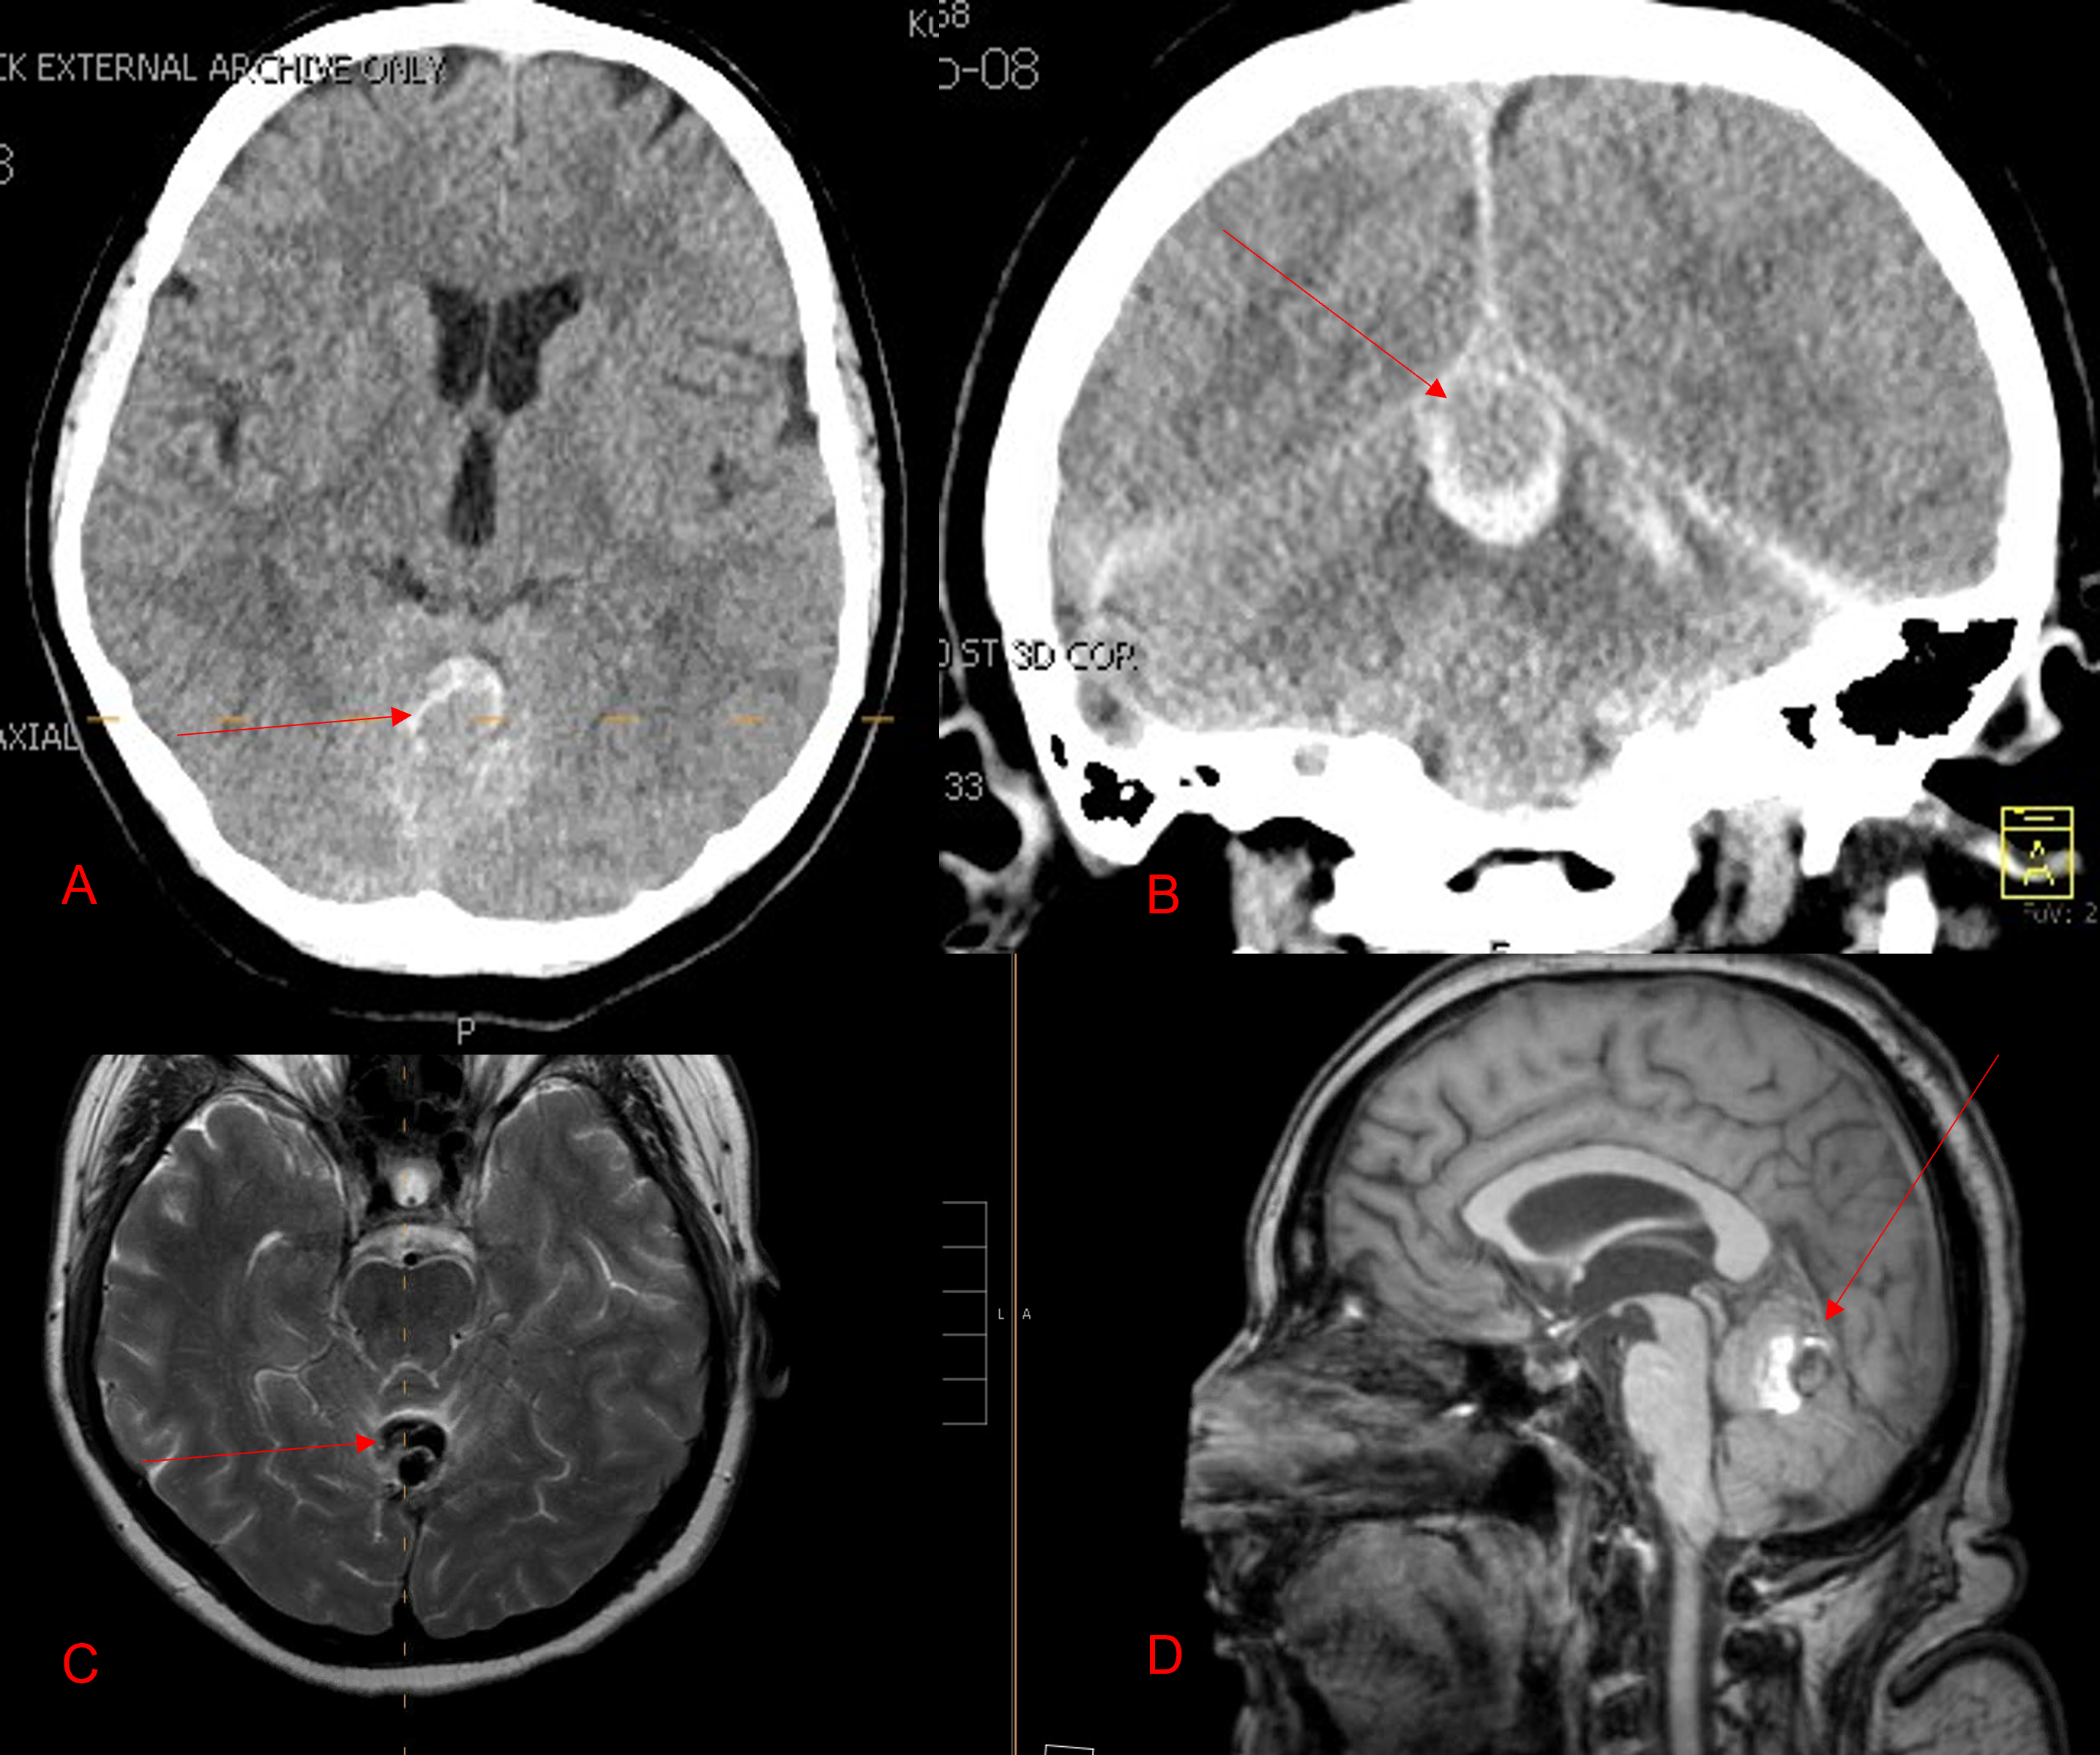

I specialize in and am very familiar with patients who have osteoporosis and require spinal surgery for degenerative lumbar disease. I am particularly interested in treating those osteoporotic patients with spinal stenosis and a concurrent spondylolisthesis or “slipped spine” or “slipped disc”. It is actually not the disc that slips in a spondylolisthesis, but one vertebra slips forward on the one below. As a result of this degenerative laxity the spine is signaled to make arthritis such as enlarged joints or thickened ligaments to compensate for the chronic instability that mainly contribute to narrowing of the spinal canal where the nerves travel. This is called spinal stenosis. Patients often see their MRI reports and note that they often have been described as having this aforementioned condition. I believe that perimenopausal, menopausal, and postmenopausal women (40-60 years of age) would benefit greatly because of their degree of activity and expectations from a new technology that my spine team is offering. However, this is not to say that men or women at any age who do require surgery would not benefit. A patient comes into the office and requires surgery to fix their slipped disc or spine and they say to me, “doctor but I have osteoporosis.” I tell them that we have available special coated screws that are designed for patients with osteoporosis that will do a much better job holding their bones together. Pedicle screws can be coated with a thin layer of hydroxyapatite (Fig 1)

(Fig 1) Hydroxyapatite Coated Pedicle Screw